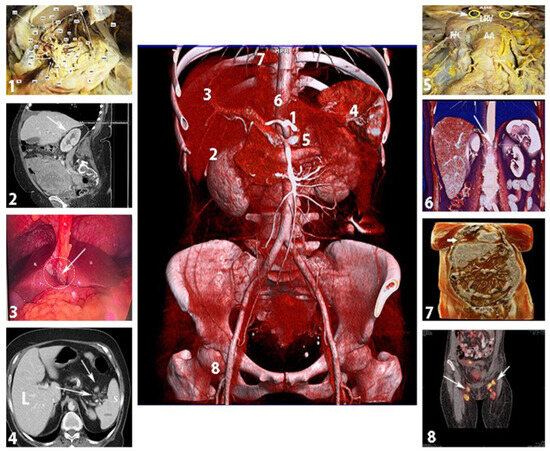

6. Suprarenal Lymph Nodes

7. Retrocrural Lymph Nodes

8. Cardiophrenic Lymph Nodes

9. Inguinal Lymph Nodes Anatomy